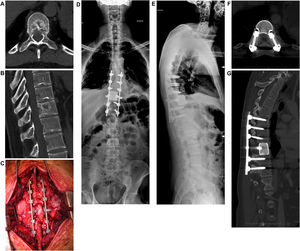

Si el paciente es considerado operable, se evalúan la extensión de la compresión de la médula espinal y la severidad del daño neurológico. De existir déficit neurológico, se evalúa la posibilidad de recuperación, sobre la base del tiempo transcurrido desde el inicio de los síntomas (figs. 2 y 3).

Mujer de 40 años. Fractura patológica en C3 derivada de metástasis espinal por cáncer de mama. Citorreducción en C3 mediante abordaje anterior, reconstrucción de la columna anterior con aloinjerto y placa de titanio. La imagen G muestra la fusión del injerto durante el seguimiento a un año.